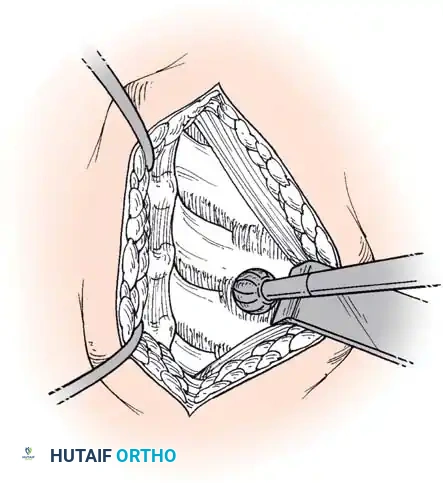

Step 2: Annulotomy and Discectomy

Self-retaining retractors are placed beneath the elevated medial borders of the longus colli. A rectangular annulotomy is performed using a #11 blade. The disc material is systematically removed using pituitary rongeurs and curettes.

Step 3: Decompression

The posterior longitudinal ligament (PLL) is carefully identified and often resected to ensure no extruded disc fragments remain in the epidural space. High-speed burrs and Kerrison rongeurs are utilized to resect posterior osteophytes and decompress the uncinate processes bilaterally, ensuring the exiting nerve roots are entirely free.